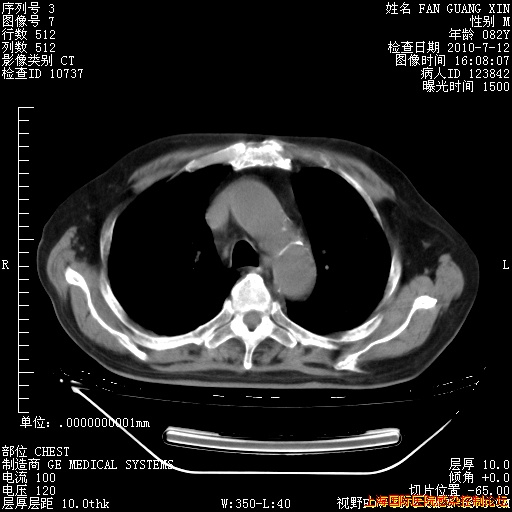

补发6月12日肺部CT肺窗

6月12日肺窗